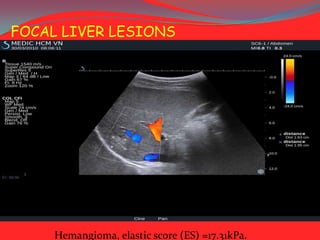

FOCAL LIVER LESIONS

Hemangioma, elastic score (ES) =17.31kPa.

Malignant tumor, V= 3.73m/sec, elastic score = 41.76kPa.